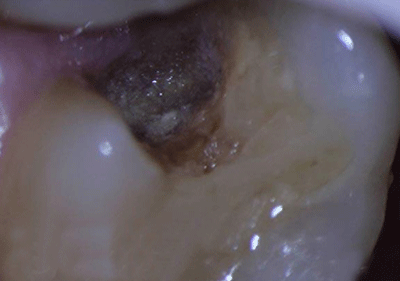

术中显微镜检查

注1:黄褐色为龋损牙体组织。

2:红色为出血点为牙髓组织(俗称牙神经),去腐未净时牙髓组织外露。